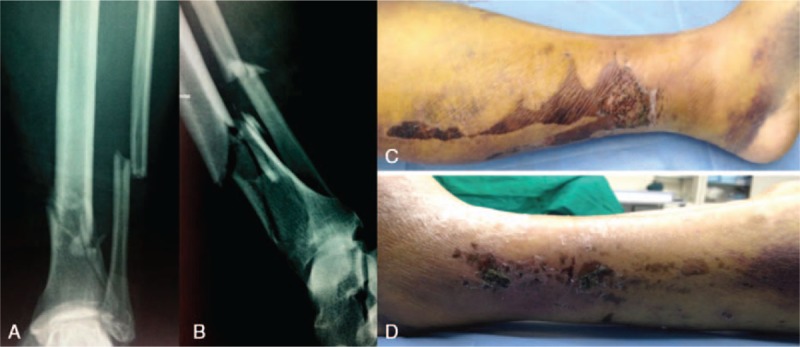

A 54-year-old woman sustained a fall and was admitted to our hospital 3 hours later with complaints of pain in the distal part of the left leg and limited mobility. On physical examination, the left distal leg showed severe swelling with several large blisters overlying the region; the distal pulses were palpable. The examination of the neurovascular system revealed no abnormalities of the lower extremities, and there was no compartment syndrome. She had no notable comorbidities. Radiography revealed fractures of the distal third of the left tibia and fibula, but the ankle articular surfaces were intact (Fig. 1A and B). Therefore diagnosis of a closed fracture of the distal third of the left tibia and fibula (AO: 43-A3) was made. Initially, strategies for detumescence and symptomatic treatment were administered. The left foot was elevated using a pillow, and oral detumescent drugs were used. A brace was used for temporary fracture fixation. Two weeks later, the swelling had alleviated and the blisters appeared wizened (Fig. 1C and D), and operative stabilization was conducted for early functional rehabilitation. The result of preoperative blood routine examination was normal.

Figure 1.

Preoperative plain radiographs and photographs. (A and B) Anteroposterior and lateral views showing fractures of the distal third of the tibia and fibula. (C and D) Photographs of medial and lateral appearance of soft-tissue injury showing the wizened blisters.